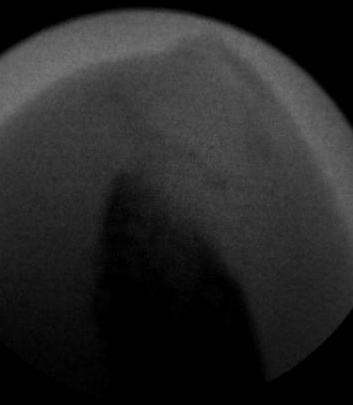

Ante un cambio en la forma y coloración de la uñas, lo primero que pensamos es que puedan ser «hongos» pero en la gran mayoría de los casos el problema está «en el interior». La uña está engrosada, puede tener alguna grieta, cambio de color y además puede ser dolorosa a la presión del calzado. Ese aspecto de «uña fea» puede ser a consecuencia de la malformación o del mal crecimiento del hueso que hay en el interior del dedo y que da lugar a esta malformación de la uña debido a que este hueso invade el territorio de todo el aparato ungueal. Digamos que la uña en vez de crecer normalmente a lo largo (longitudinalmente) crece a lo alto (verticalmente) dando ese aspecto de «uña enferma». Por ello, para un buen diagnóstico es necesario un estudio radiológico donde poder observar esa excrecencia de hueso que dará lugar a ese mal crecimiento de la uña. Las imágenes radiológicas nos van a mostrar ese montículo en el hueso causante de la deformidad de la uña.